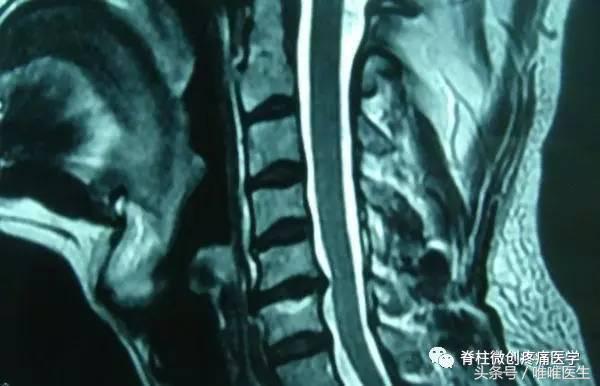

4.颈椎MRI检查

颈椎的MRI检查主要用于诊断颈椎间盘突出(目前,MRI成像技术是对椎间盘病变进行检查的最有效的方法。因为MRI成像对组织密度的分辨率高。无需作其他的创伤性检查,即能分辨正常纤维环与髓核。

并显示椎间盘突出的方向与程度,了解椎间盘有无变性,在这方面其优于CT。),观察颈椎后纵韧带钙化症,排除脊髓肿瘤及脊椎肿瘤,明确颈椎外伤和感染的病变程度。同样,MRI也是诊断椎体、椎间隙感染最有效、最特异的检查方法。

MRI检查还可以用于明确先天性畸形的疾病诊断,排除动静脉的畸形等。